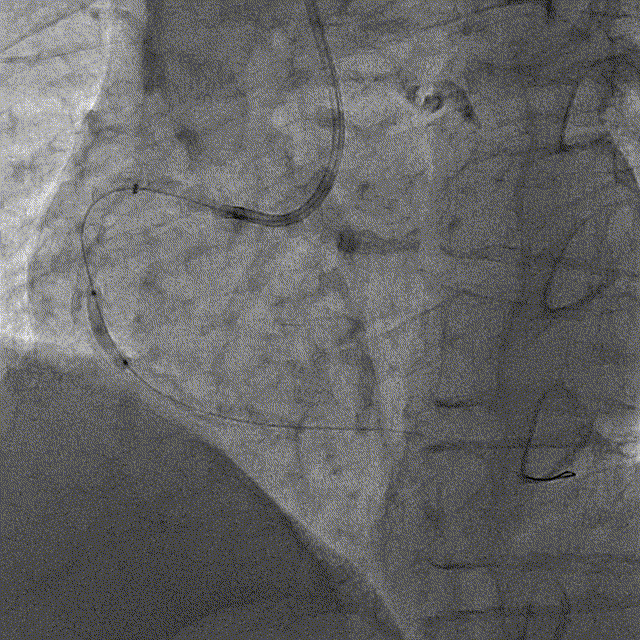

冠脉造影

冠脉造影结果:LM外膜钙化,内膜不光滑,中段狭窄90%,TIMI3级。LCX外膜钙化,内膜不光滑,TIMI3级。RCA外膜钙化,内膜不光滑,近段狭窄80%,中段狭窄90%,可见破损斑块,TIMI3级。

冠脉内介入治疗